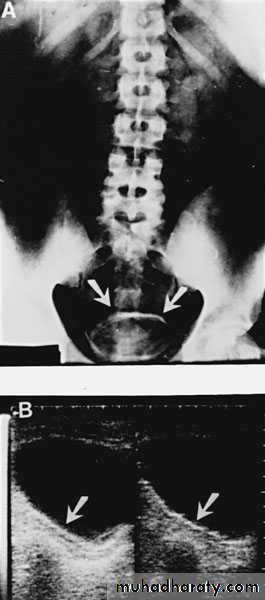

U/S: cystic cortical lesion with internal echoes.

IVU: space occupying lesion, which may be confused with renal tumor.

U/S cystic lesion with internal echoes (renal abscess)

Retrograde pyelography:

Left renal abscess

CT scan: right renal abscess

CT scan: Left renal abscess